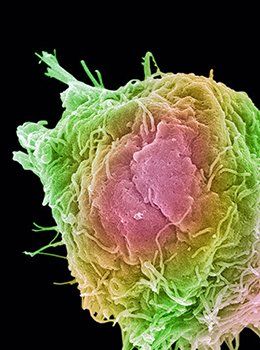

The Wonderful World of 3D+